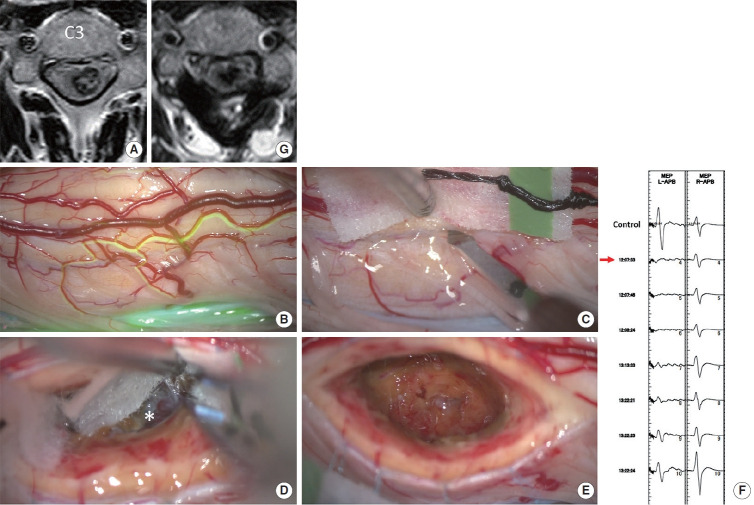

目的:髓内出血(IH)合并高颈海绵状畸形(CM)仍然是神经外科医生面临的一个重大挑战。本研究旨在评估后外侧沟(PLS)入路治疗这些复杂病例的有效性和安全性。方法:本单中心回顾性研究包括近4年来58例经手术治疗的脊髓髓内肿瘤。在IH侧采用PLS入路切除CM。术前、术后一周及最近随访时采用改良的McCormick功能量表(MMCS)评估神经功能。结果:从数据库中确定了6例伴有C3水平以上CM的IH患者。平均年龄31.2岁,女性4例。术前症状持续时间为0 ~ 48个月。所有6例患者均实现了CM的完全切除,未发生包括呼吸系统并发症在内的严重不良事件。平均随访时间为21.7个月。术前MMCS平均评分为3.0分,术后早期维持在2.5分,最近一次随访进一步提高到2.2分。1例腹侧型CM患者在初次手术后30个月在同一水平再次出血。该患者随后接受了第二次手术,采用前外侧沟入路,耐受性良好。结论:PLS入路即使在高颈椎处也能安全切除CM。然而,腹侧型CMs仍然是外科关注的主要问题。

Results: Six patients with IH associated with CM above the C3 level were identified from the database. The mean age was 31.2 years, and 4 of the 6 patients were female. Symptom duration prior to surgery ranged from 0 to 48 months. Total removal of the CM was achieved in all 6 cases without any serious adverse events including respiratory complications. The average follow-up duration was 21.7 months. The mean MMCS score was 3.0 before surgery, maintained at 2.5 in the early postoperative period, and improved further to 2.2 at the most recent follow-up. One patient of ventral-type CM experienced recurrent hemorrhage at the same level 30 months after the initial surgery. This patient subsequently underwent a second surgery using the anterolateral sulcus approach, which was well tolerated.